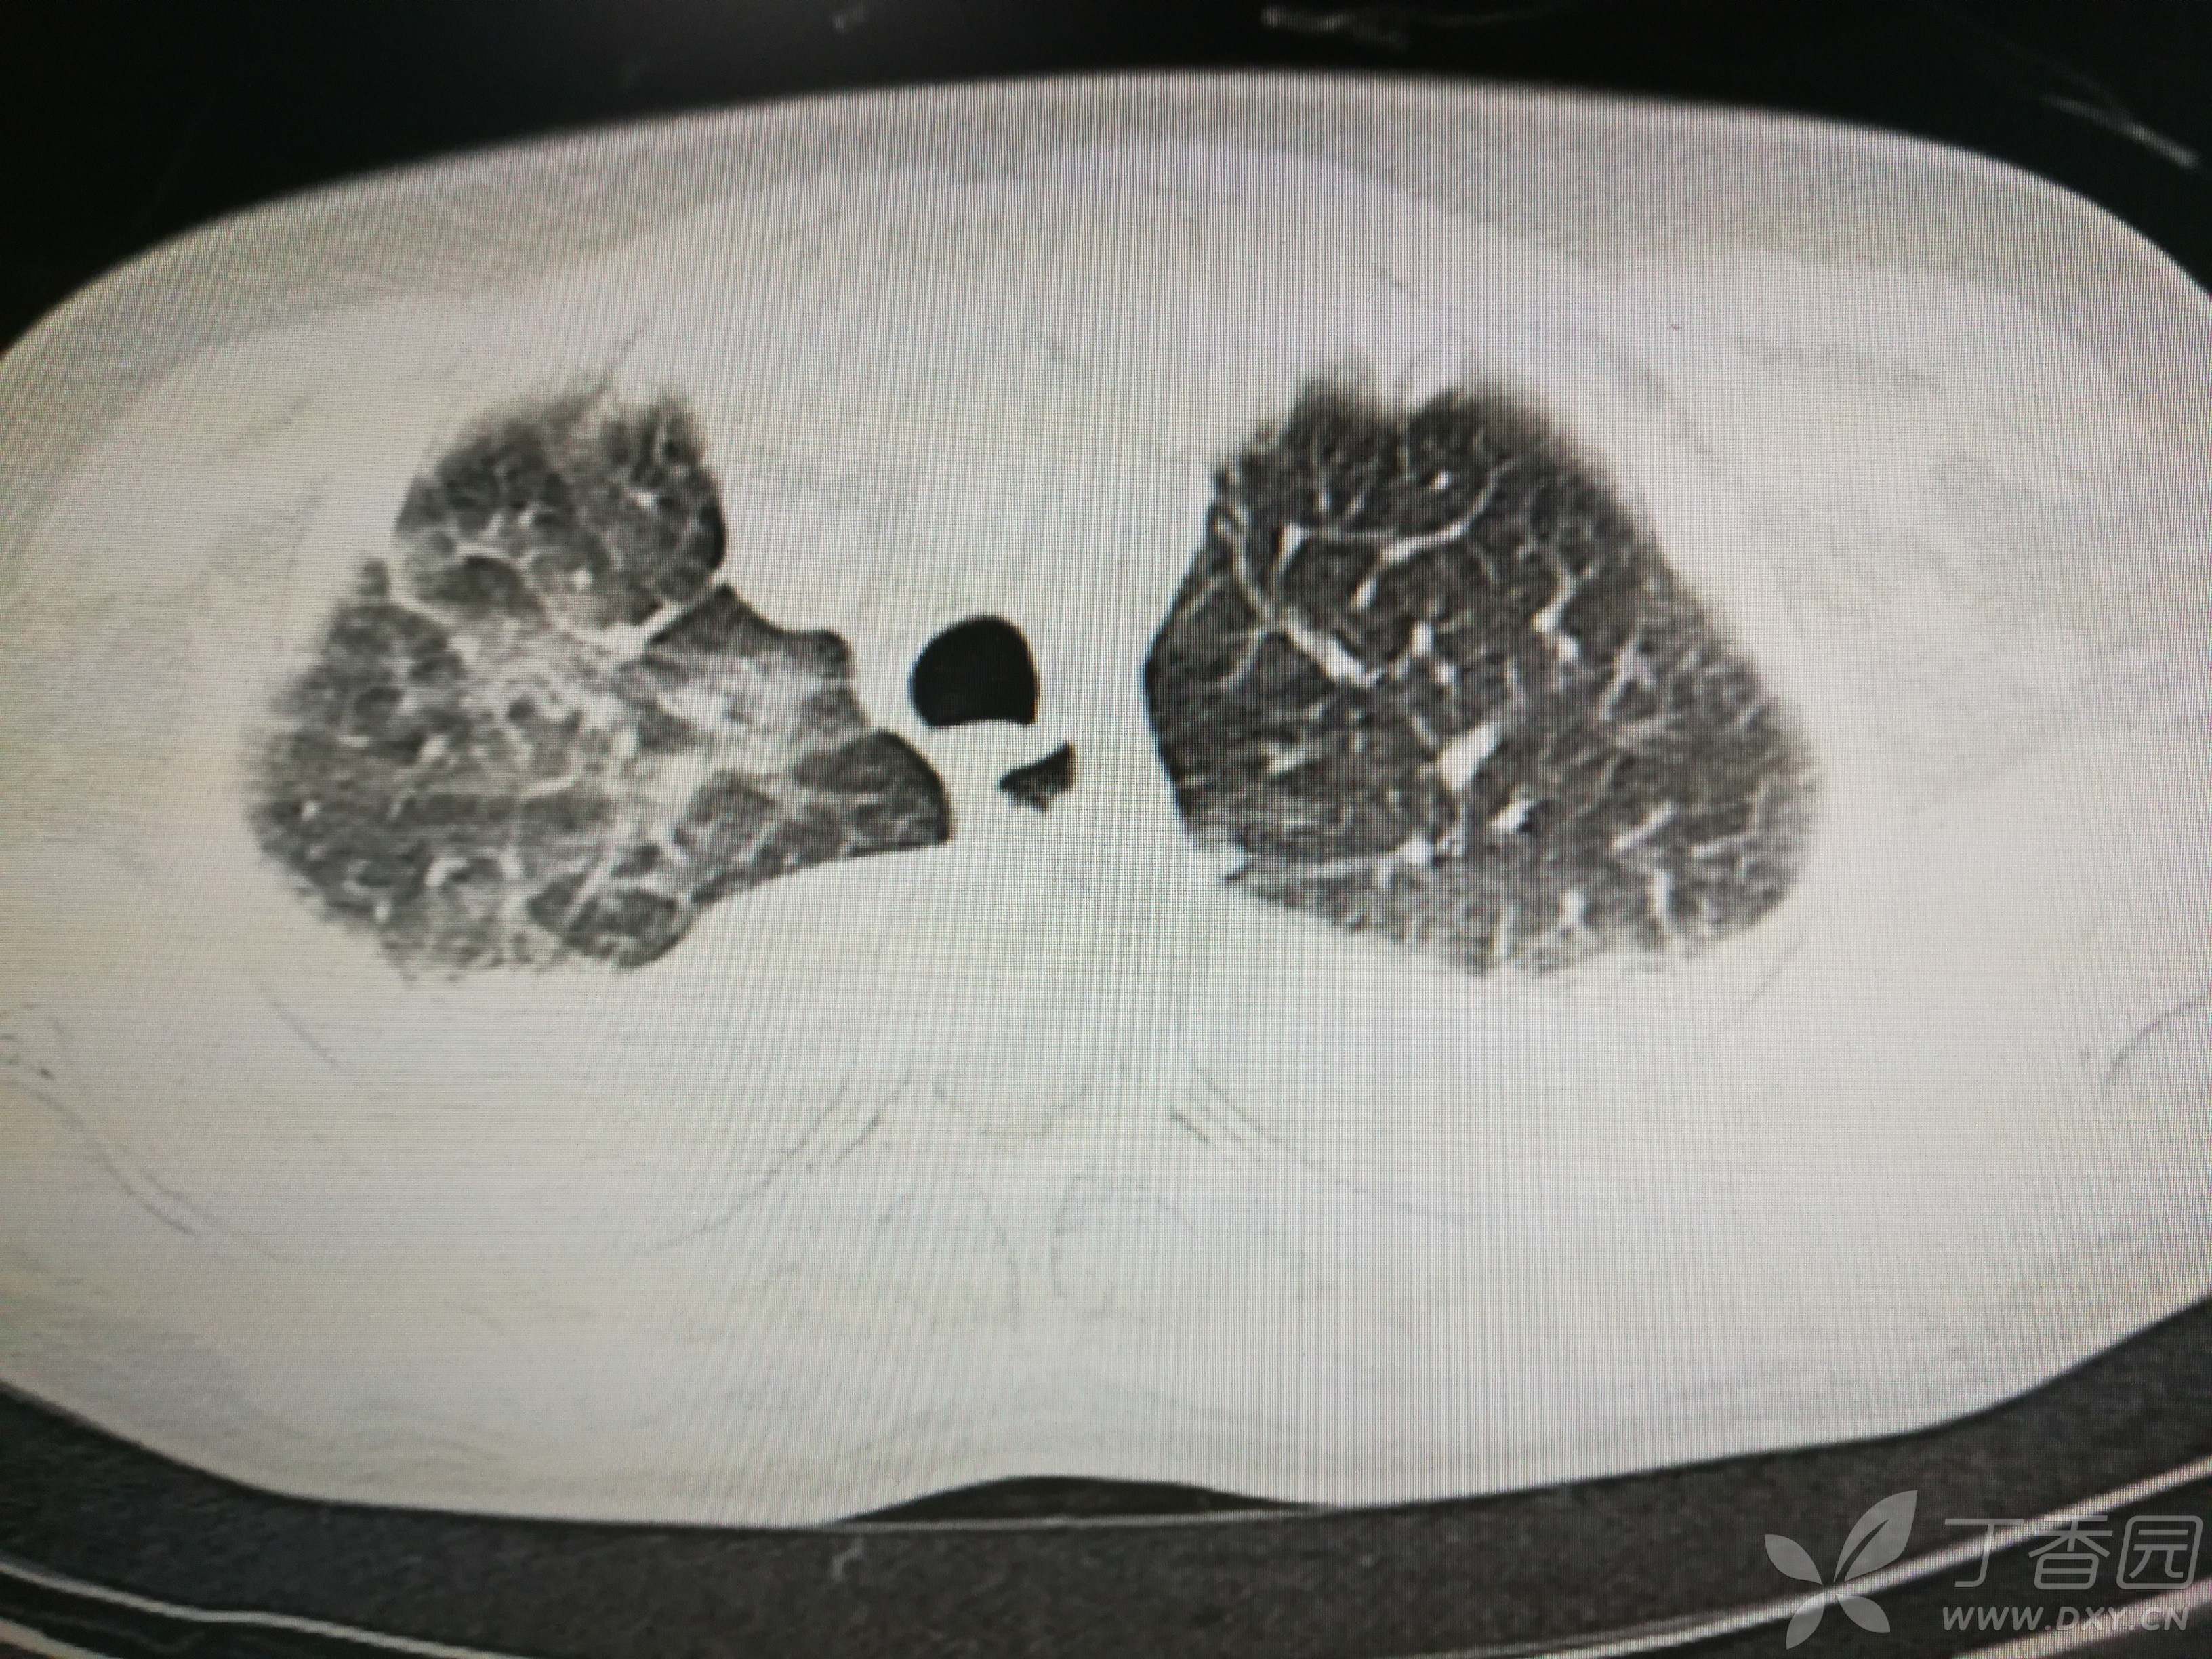

给予低分子肝素钙针抗凝、七叶皂苷钠针消肿及骨牵引固定等等治疗。入院后第四天行“左侧股骨下段骨折切开复位内固定术”(术前查双下肢彩超:双下肢深静脉血流通畅),手术顺利,术后予预防感染、预防血栓形成等治疗。术后患者无明显发热,生命体征平稳。术后第四天复查血常规:白细胞13.4×109/L,血红蛋白84g/L,血小板在正常范围。生化:白蛋白35.7g/L,余无明显异常。当天,患者开始出现轻度胸闷气急,可耐受。术后第五天患者胸闷气急加重,无胸痛,无背痛,无咯血,无意识障碍,无头晕头痛,无恶心呕吐等,急查凝血功能:纤维蛋白原降解产物12mg/L,D二聚体4000ug/L,余无明显异常。查动脉血气分析:pH7.52,氧分压62mmHg,二氧化碳分压30mmHg,碱剩余1.8mmol/L,乳酸1.0mm/L,血红蛋白86g/L。查胸部CT见下(先视频后图片):